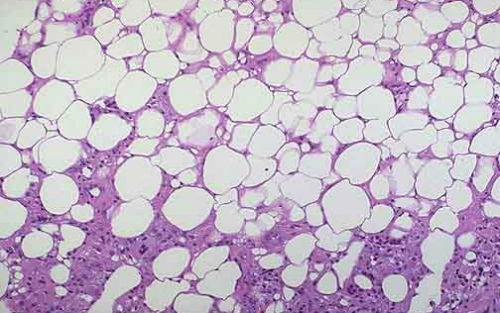

White fat stores energy in the form of triglycerides, and, depending on their location in the body, may have a negative effect on health, leading to insulin resistance, metabolic syndrome and type 2 diabetes. Morphology and function of brown fat cells are different, can be stored as fat burning energy while consuming glucose. Beige fat cells burn energy, can be embedded in white adipose tissue. Because these fats play an important role in various diseases, so by the scientists' attention.

Scientists have long sought a way to be able to increase brown fat. But in addition to the body white fat and brown fat, but there is a third type of fat - the so-called beige fat. Like brown fat as beige fat can burn calories and generate heat. More importantly, it is possible to prevent obesity plays an important role.